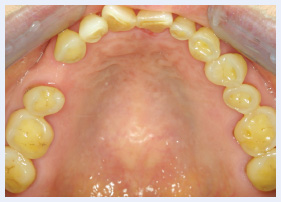

Grinding And Clenching Bruxism Pocket Dentistry Bruxism (brucks is im) is a habit of grinding or clenching your teeth. it can happen in children or adults of any age. people who suffer from bruxism may have one or more of these symptoms: how is bruxism treated? treatment depends on each person’s situation. your dentist may recommend one or more of the following treatments:. People may be oblivious to their bruxism, but family members might notice it. bruxism can abrade and eventually wear down enamel and dentin in the crowns of teeth, damage metal or ceramic dental crowns, and cause teeth to become mobile.

Grinding And Clenching Bruxism Pocket Dentistry Bruxism is a condition where a person grinds, clenches, or gnashes his or her teeth; it can occur when awake or asleep. bruxism that happens while a person is awake is more common, but bruxism that happens during sleep has been studied more. children as well as adults can have this condition. When stressed, your jaw muscles tend to tighten, resulting in teeth grinding and or clenching (also called bruxism). while this can happen without you even realizing it, it can be very dangerous to your teeth. there are lots of techniques you can use to lessen the effects of bruxism. Left untreated, bruxism can cause jaw pain and dental damage. learn more about treatments that can help you stop grinding your teeth. In the context of bruxism, grinding is characterised by dynamic tooth contacts brought about by jaw muscle activities. grinding may or may not be accompanied by sounds. bracing is the equivalent of clenching, but without tooth contact.

Grinding And Clenching Bruxism Pocket Dentistry Left untreated, bruxism can cause jaw pain and dental damage. learn more about treatments that can help you stop grinding your teeth. In the context of bruxism, grinding is characterised by dynamic tooth contacts brought about by jaw muscle activities. grinding may or may not be accompanied by sounds. bracing is the equivalent of clenching, but without tooth contact. Bruxism, characterized by involuntary grinding or clenching of teeth, is a widespread condition with multifaceted implications for oral health, physical well being, and quality of life. Studies show that changes in brain activity like low dopamine, high stress, and poor sleep can all contribute to teeth grinding. dentists can treat the damage caused by bruxism, but understanding the cause is what helps prevent it from coming back. See your dentist or other healthcare professional if you have symptoms that could be caused by grinding or clenching your teeth or if you have other concerns about your teeth or jaws. This series of papers will review the aetiology of bruxism, its impacts and treatment strategies for persistent bruxers who are at risk of, or suffering, tissue damage.